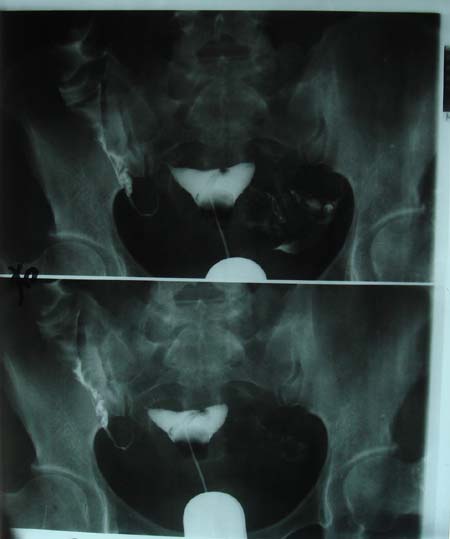

以下是引用dyqct在2009-8-23 16:17:00的发言:[br]考虑:1、造影剂进入腹腔、结肠旁沟、肝周;[br] 2、子宫明显增大(腺肌增生症?);[br] 3、膀胱显影是由于造影剂吸收后经肾分泌进入膀胱的;[br] 4、建议mri检查子宫。